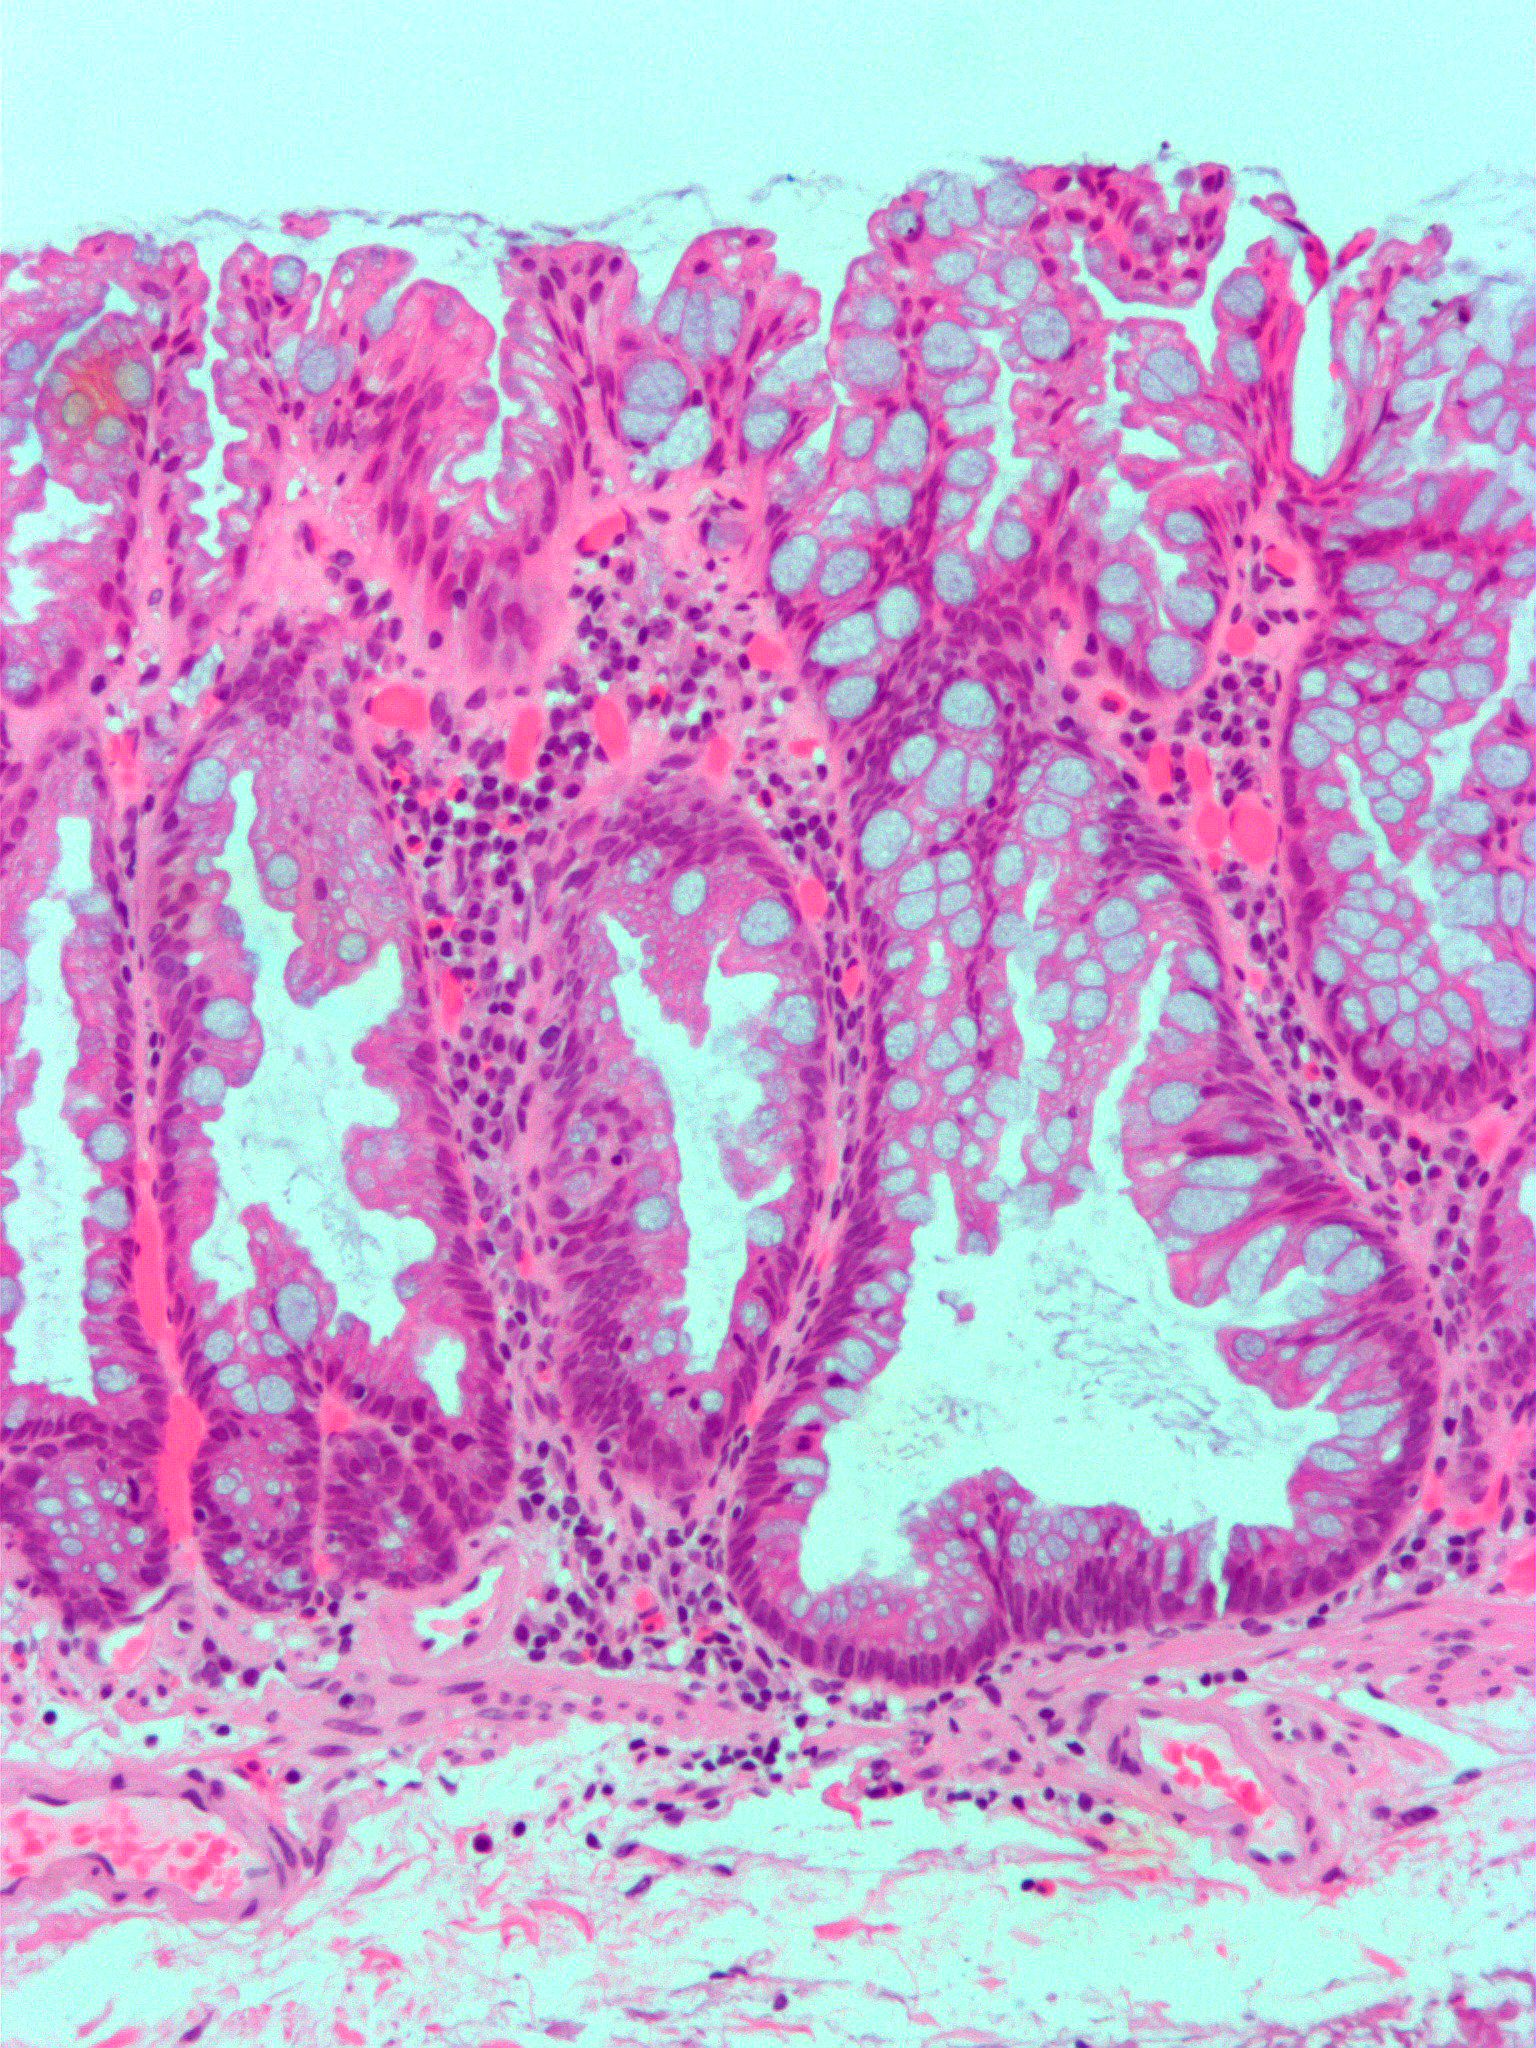

| 위 과형성 용종 | 위 | 부종성 및 염증성 기질로 분리된 신장되고 뒤틀린 낭포성 와상 | ![]() | 위 과형성 용종증 | |

| 위 과형성 용종 | 위 | 부종성 및 염증성 기질로 분리된 신장되고 뒤틀린 낭포성 와상 | 위 과형성 용종증 | ||